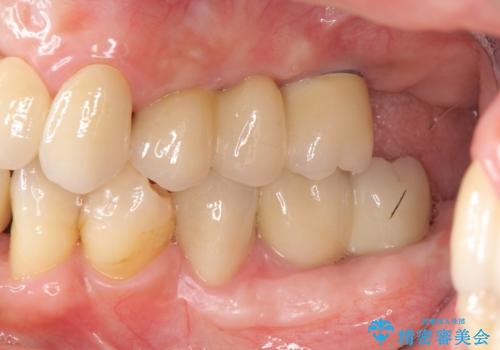

歯周病 全顎治療

- 前歯の見た目、入れ歯による噛めないことの改善を求めて来院されました。

検査により全顎的な歯周病治療、欠損のインプラント補綴、根管治療が必要な状態であることをお伝えし、治療を計画します。